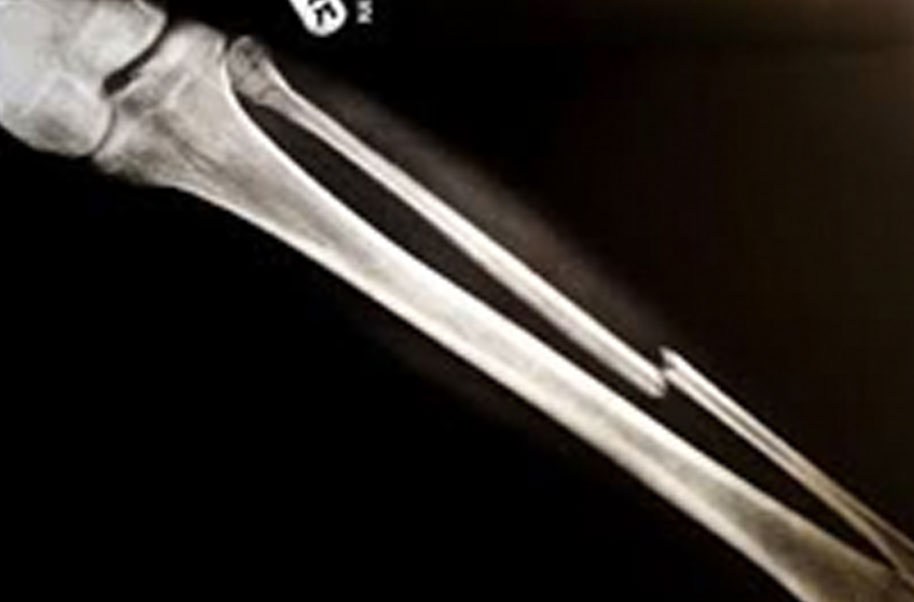

Os Temporale (Broken Bone)

A complete or partial break in a bone.

- Treatment often involves resetting the bone in place and immobilising it in a cast or splint to give it time to heal. Sometimes, surgery with rods, plates and screws may be required.

Causes of bone fractures include trauma, overuse and diseases that weaken bones.